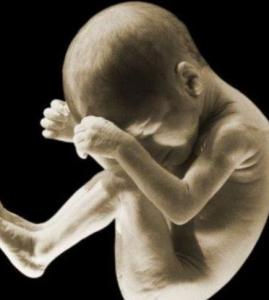

我们能够发现从确定妊娠之日起,孕妇的检查就非常重要,尤其是针对妊娠14-21周这个时间段里,进行相应的检查是对宝宝健康、孕妇健康的保障,大家切记不可忽视!

除此之外,在备孕之前必须要进行一系列检查,包括了各种病毒的检查,所以在孕检过程当中,准妈妈必须要多加关注这方面的信息。很多体质偏弱的备孕女性,往往在感染到各种病毒的机率较高,并且这样很容易传染给胎儿,进而出现胎儿畸形问题的产生。